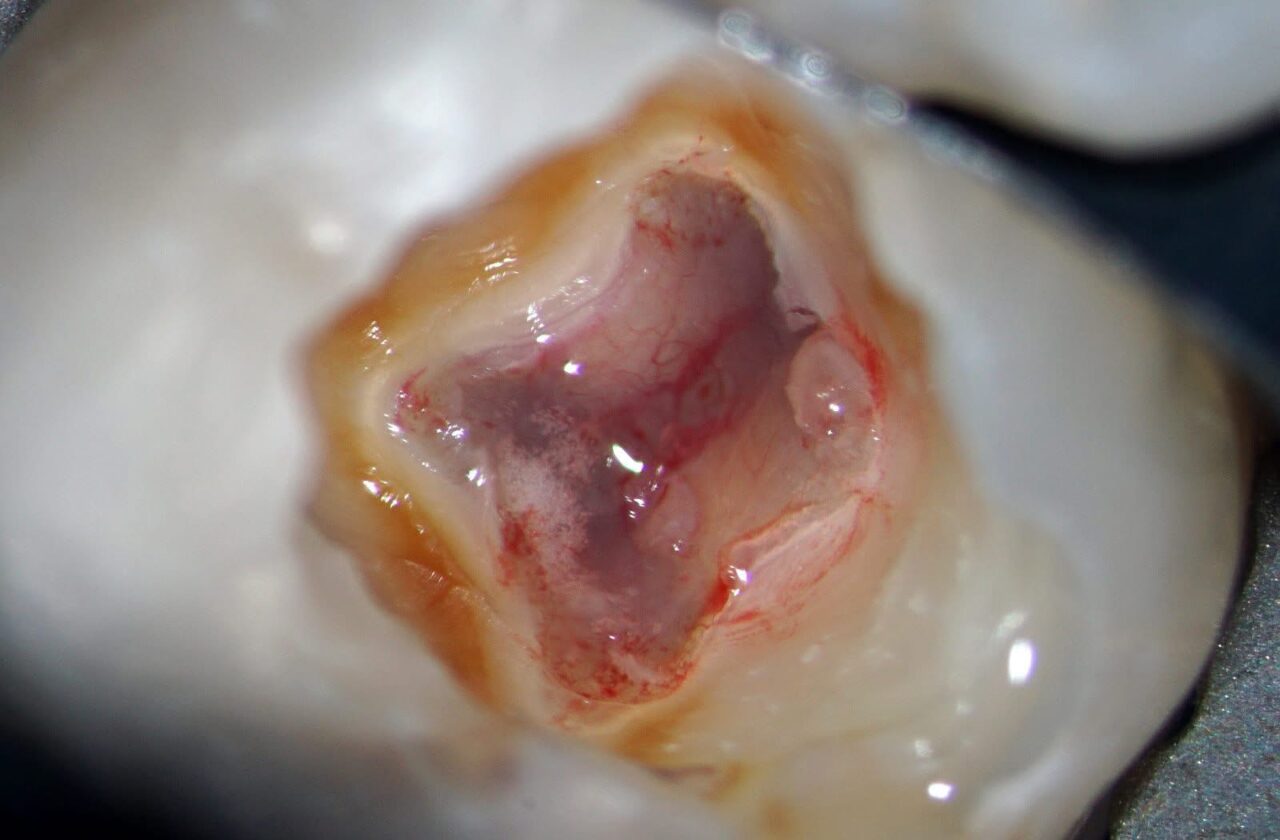

麻酔をした後にラバーダム防湿をして、随腔内を明示した写真です。